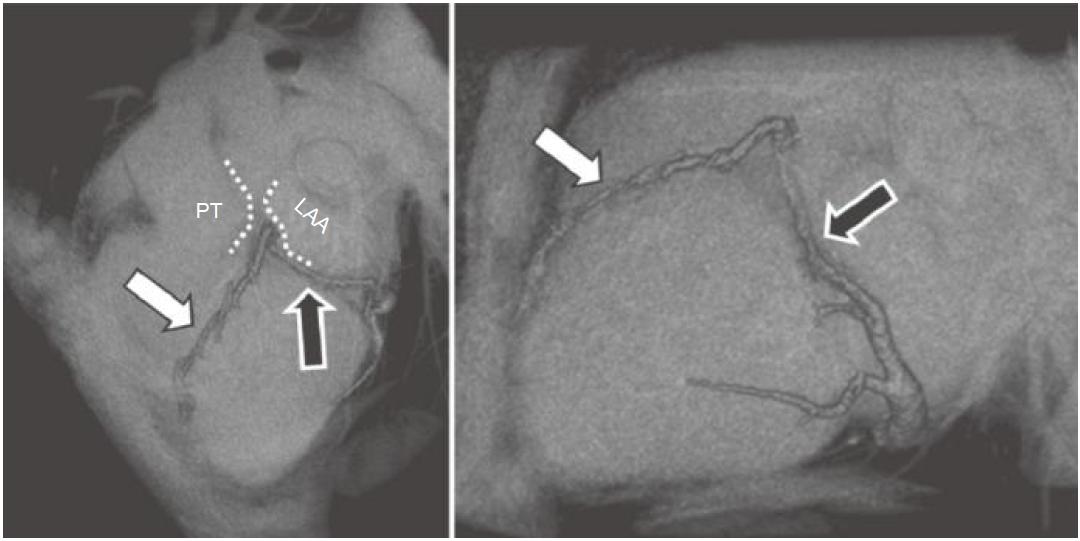

图13-6 前室间静脉(白箭)从心尖至心底走行于前室间沟,穿过肺动脉主干(PT)及左心耳(LAA)进入左房室沟,成为心大静脉(黑箭)

图13-7 心脏左侧面观,心大静脉(黑箭)接收来自左缘静脉(*)的血流。将左心房斜静脉(箭头)与心大静脉的汇合处定义为冠状窦的起点,冠状窦接收来自左心室下静脉(双箭)及心中静脉(白箭)的血流

★ 前室间静脉起源于前室间沟,通常位于心尖部(图13-6)。

★ 尽管前室间静脉通常走行于肺动脉主干与左心耳之间,但在其离开前室间沟的位置常见变异。

★ 前室间静脉从左侧进入左房室间沟后,成为心大静脉。

★ 前室间静脉接收来自左心室远端的静脉血流。